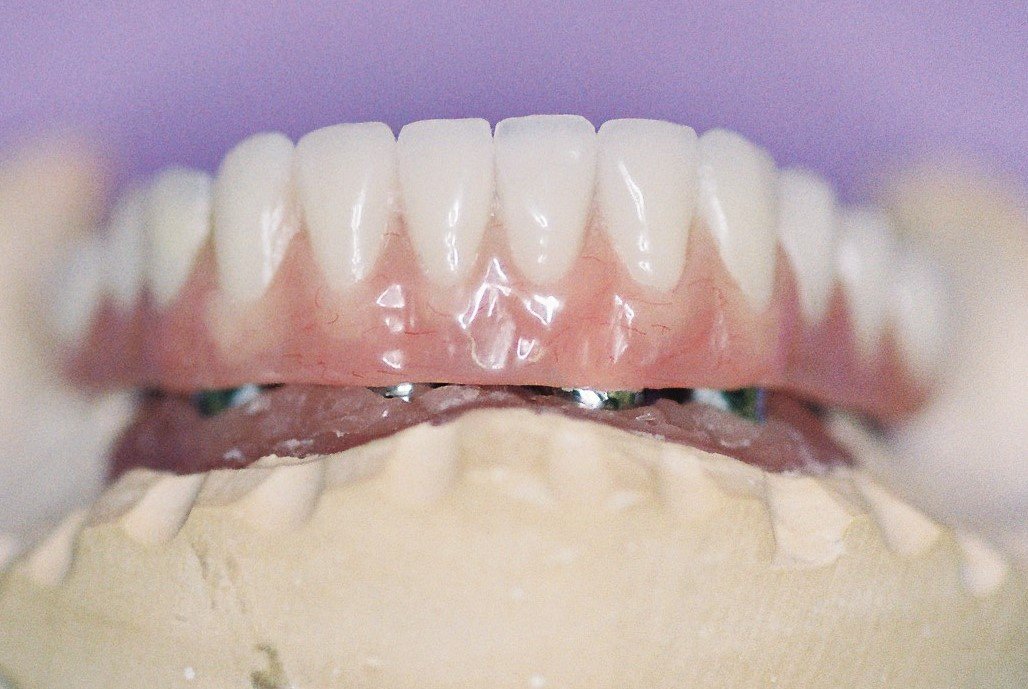

THIS IS A VIEW OF A PLASTER MODEL OF THE PREPARED TEETH AND SHOWING THE UNDER SURFACE OF THE 3 UNIT ZIRCONIA/PORCELAIN BRIDGE. PLEASE NOTE THE BRIDGE TOOTH HAS AN EGG LIKE OR SPHERIODAL SHAPE WHICH RECESSES INTO THE GUM LINE FOR AESTHETICS AND FUNCTION.”

NOTE THE COMPLETED CERAMIC 3 UNIT BRIDGE AND CROWN ON A PLASTER MODEL WHICH THE CERAMIST DUPLICATED USING DOUBLE SCANNING TECHNOLOGY, TO RE-CREATE THE SIZE AND SHAPES OF THE ORIGINAL TEMPORARY CROWN AND BRIDGE.